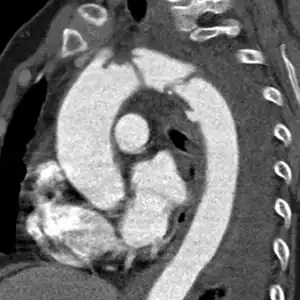

CT scan showing an extraluminal hematoma of the distal aortic arch containing an aortic rupture

The condition is often suspected in patients close to death with abdominal trauma or with relevant risk-factors. Diagnosis may be confirmed by ultrasound or CT scan.